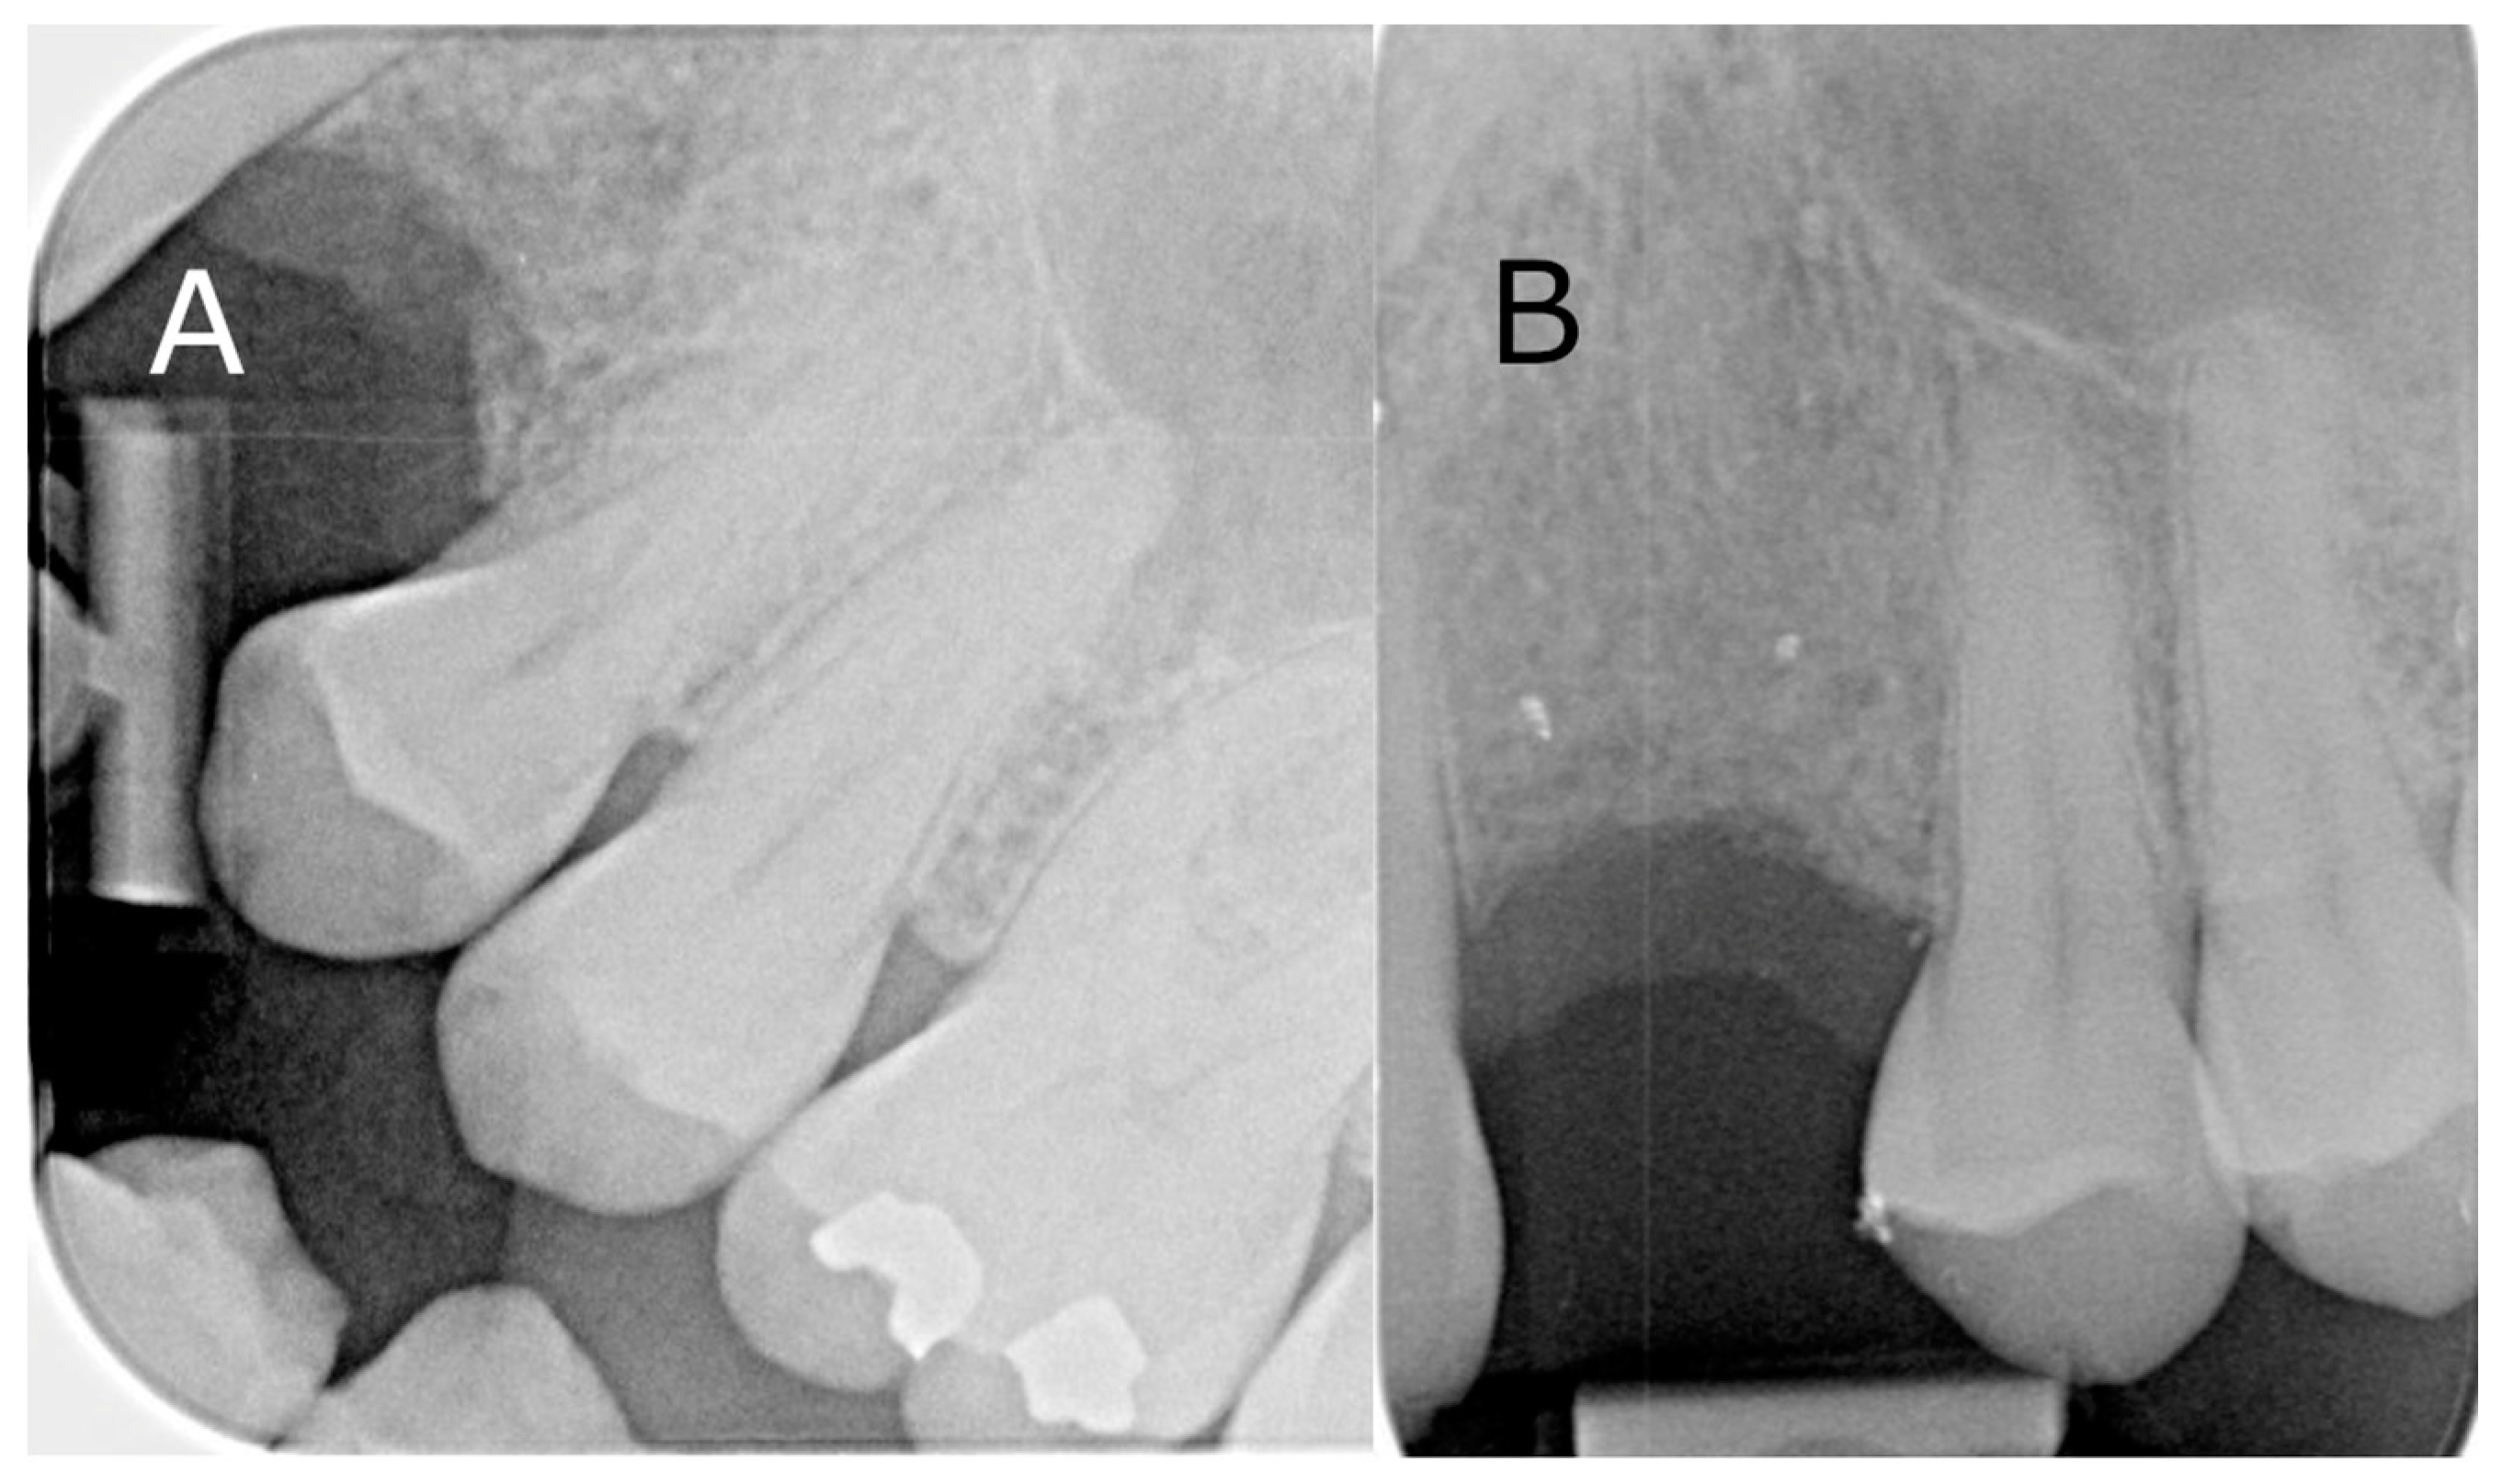

A 49-year-old male patient presented requesting restorative options for a missing 23. A dental implant was proposed as a treatment option, and the patient consented to proceed. During screening with OPG and CBCT, a submerged radiopaque GP was observed. The GP intersected the ideal implant position (Figure 5A). It was decided that it would be removed utilising a surgical guide to minimise cortical plate loss for bone preservation prior to implant placement. The treatment plan was discussed with the patient, and informed consent was obtained. Local anaesthesia with 4% articaine containing 1:100,000 adrenaline was administered via buccal, palatal, and mid-crestal infiltrations. A mid-crestal incision and vertical relieving incisions were performed. A full thickness periosteal flap was raised at the left canine region to expose the alveolar ridge. The surgical guide was placed over the exposed ridge to indicate the position of the retained GP and subsequent corticotomy. A Ø 1.4 mm small round bur was then inserted through the surgical guide channel to remove the cortical plate to reveal the GP (Figure 5B). The GP was removed with a small spoon excavator, and a periapical radiograph was taken to ensure the complete removal of restorative debris (Figure 5C). The width of the osteotomy site was 3 mm at the apical end and 2 mm at the coronal end (Figure 5D). The Bio-Gide membrane (Geislitch) was placed over the osteotomy site to prevent soft tissue growth into the defect and enable fibroblast attachment for the formation of new bone tissues and blood vessels in the defect. No bone substitute material was used. The flap was repositioned and secured with six simple interrupted sutures using PROLENE suture 5-0 (Ethicon). The surgical site was reviewed at 6 and 12 months post-operatively, with intraoral radiographs confirming the complete removal of the GP (Figure 6).

Figure 6. Intraoral radiographs of the surgical site from the precision osteotomy: (A) 6-month follow-up; (B) 12-month follow-up.